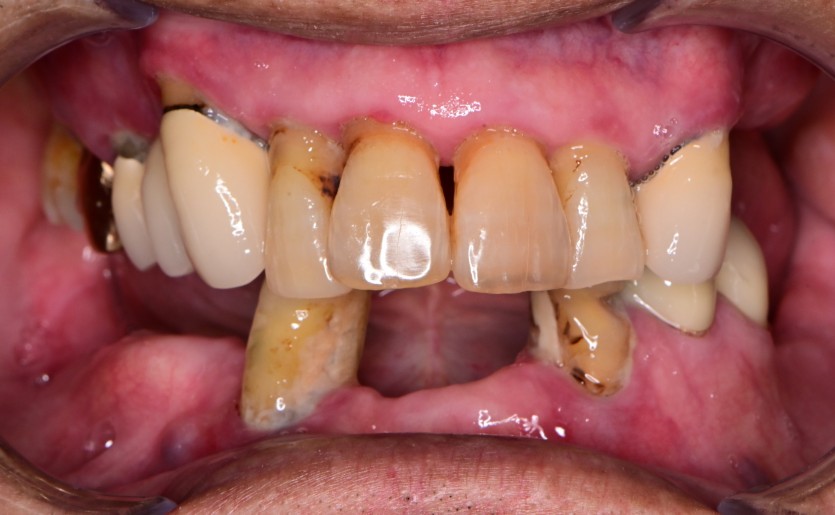

전체 임플란트 증례입니다.

18개의 임플란트로 완성하였습니다.